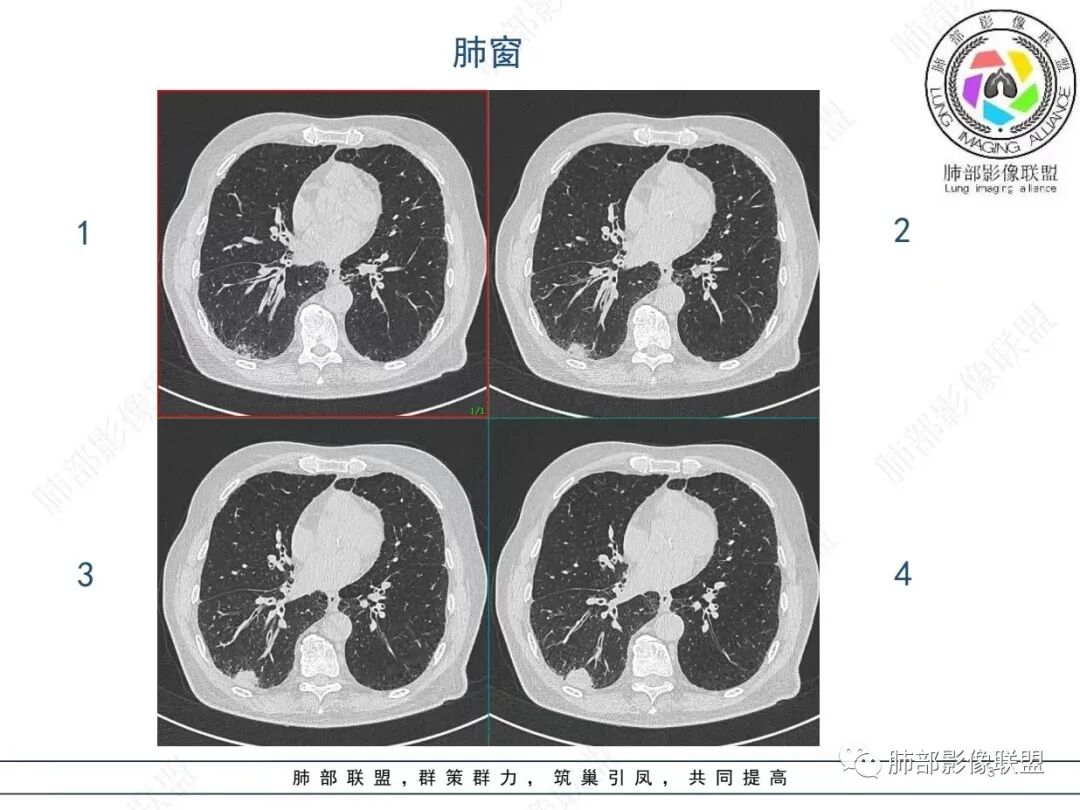

老年男性,发作性气喘,实验室检查白细胞增高。肺部影像表现:右肺胸膜下占位性病变,肺气肿背景,内部可见空腔/空泡影,周围可见小结节,增强动脉期明显强化,静脉期及延迟期强化减低,右侧肺门可见肿大淋巴结,有吸烟史,近年减少,首先考虑恶性肿瘤,肺小细胞癌/鳞癌,隐球菌作为鉴别诊断,病例穿刺活检。

老年男性,气短,胸痛半年,考虑慢性病史,无发热,常见的肺部感染可以排除,右肺下叶基地段靠近胸膜实变影,边缘清楚,不均匀强化,可见空泡征,点状血管影,周围小叶中央型结节,有网格影,支气管扩张,磨玻璃影,肺间质改变,右侧肺门淋巴结肿大,综合考虑恶性肿瘤并肺内转移

老年男性,胸疼入院,影像表现,右肺下叶胸膜下结节,边界清晰,与支气管关系不密切,病灶内见空洞?增强病灶均匀强化,右肺门可见增大淋巴结,考虑恶性病变,小细胞癌,其次鳞癌

老年男性,肺气肿背景,右肺下叶,右肺下叶胸膜处实性结节,形似山丘,有分叶,病灶内可见扩张细支气管/空泡,边缘可见弯曲血管,增强后不均匀强化,可见血管影,病灶胸膜侧呈小波浪??状,局部突入胸膜面,右肺门肿大淋巴结。考虑恶性结节,小细胞肺癌,腺癌,鉴别炎性肉芽肿。建议ct下穿刺活检。

老年男性,肺气肿病史,支气管束增粗,管壁增厚,右肺下叶后基底段胸膜下肿块,土豆征,边界清,有膨隆,小支气管边缘阻断,见集血管束征,肿块强化明显(快进快出特点),并偏心空洞,胸膜下栽赃,周围肺结构破坏(蜂窝状影表现),右肺门淋巴结转移肿大,血管内皮生长因子偏高,肿块与小支气管,血管束关系密切,强化特点,定恶性肺肿瘤,小细胞Ca。

老年男性,肺气肿,右肺下叶胸膜下结节,边缘毛躁,周围多发间质增厚,临近胸膜下脂肪间隙模糊,增强后动脉期不均匀强化,延迟期强化较低,右肺门肿大淋巴结,考虑恶性,鳞癌,小细胞肺癌,鉴别炎性肉芽肿性结节

右肺下叶胸膜下结节,边界清,边缘平直膨隆,血管集束,其内空洞,明显不均匀强化,考虑腺癌?小细胞癌?鉴别隐球菌

肺气肿,胸膜下结节,边界清晰,边缘毛糙,病灶内见空洞,增强病灶均匀强化,右肺门可见增大淋巴结,考虑恶性病变,小细胞癌,其次鳞癌,鉴别隐球

老年男性,肺气肿背景,右肺下叶胸膜下团块影,明显强化,其内空泡征,周边血管聚集,右肺门淋巴结增大,考虑腺癌?

右下叶胸膜下结节,宽基底与胸膜相连,结节与胸膜相交呈钝角〈山丘征〉,内可见充气扩张的支气管,中度强化,结节边缘无毛刺,内见走行自然的血管影,提示破坏力及收缩力差,右肺门可见肿大淋巴结,老年烟民,考虑恶性占位,支持小细胞癌

右肺下叶胸膜下结节,呈山丘状,生长在慢支肺气肿间质纤维化的基础上,边缘相对光滑清晰,右肺门淋巴结肿大,强化呈速升速降,老年男性,吸烟史,考虑小细胞肺癌,鉴别隐球

男,80,发作性气喘半年,加重1天。长年大量吸烟史。肺部CT:肺气肿背景,右肺胸膜下实性占位,处于外周大疱带与气肿带交界,山丘征,边缘膨隆,边界较清,血管集束,周围可见小结节。增强不均匀强化,内可见迂曲模糊血管影,右肺门、隆突下可见肿大淋巴结。首先考虑恶性肿瘤,小?鳞?鉴别PC、TB等。